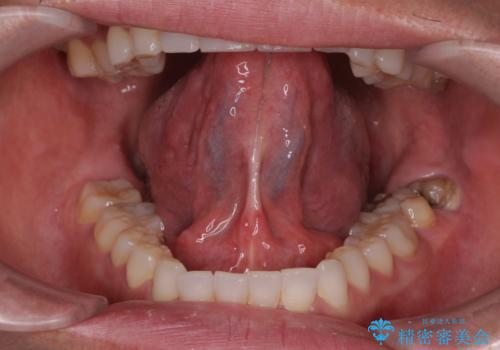

[舌小帯の形成術] 舌の動きが悪い 滑舌を改善したい!

担当医 大元洋佑